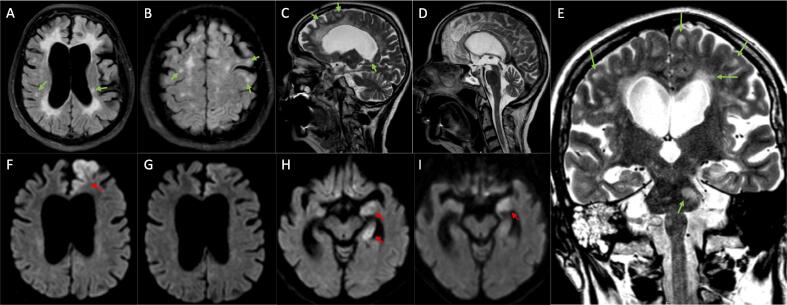

We present the case of a 73-year-old Caucasian woman with secondary progressive multiple sclerosis (SPMS). The patient had been diagnosed with MS decades ago, but the corresponding MRI images and written records were unavailable due to various changes in healthcare providers. However, we performed MRI and the findings were consistent with advanced MS (please see Fig. 1 A-E) and, along with the application of the 2017 McDonald criteria, supported the diagnosis of MS. Hence, she wasn’t tested for anti-MOG and anti-AQP4 antibodies.[10] The patient was bedridden due to MS-related spastic tetra-paresis. According to information provided by the husband, there were presumed mild chronic psycho-organic alterations, including impaired memory and sleep disturbances. To the best of our knowledge, the patient had not received any immunomodulating therapy. There was no history of epileptic seizures. We had previously encountered the patient two years ago when she was hospitalized for left-sided idiopathic peripheral facial palsy, which resulted in a residual Bell phenomenon. Before admission, she was taking retarded fampridine 10 mg/day, baclofen 10 mg/day, and opipramol 100 mg/day.

Fig. 1.

Bihemispheric, subcortical, and juxtacortical FLAIR (Fluid-Attenuated Inversion Recovery) (A, B) and T2 (C, D, E) hyperintensities with multiple disseminated ovoid lesions, partially located in association with the corpus callosum, periventricular or in the pons (E) (exemplarily marked with green arrows). The partially visualized cervical myelon (D) shows no abnormalities. (A) shows brain atrophy with significant enlargement of the ventricles and subarachnoid spaces. Brain Diffusion-Weighted Imaging with (F) areal restricted diffusion of the left frontal lobe, particularly the parasagittal cortical zone before and (G) 13 days after IV prednisolone treatment. (H) Restricted diffusion of the left medial temporal lobe before and (I) 13 days after IV prednisolone treatment (marked with red arrows). (For interpretation of the references to colour in this figure legend, the reader is referred to the web version of this article.)

Due to persistent symptoms and the emergence of new vegetative symptoms such as sub-febrile temperature, hyperhidrosis, and blood pressure fluctuations with pleural effusions, CSF analysis was repeated, showing a lymphocytic pleocytosis of 11 cells/µl. DWI (Diffusion-Weighted Imaging) revealed restricted diffusion in left brain areas including the frontal and temporal lobe, hippocampus, and corpus amygdaloideum (Fig. 1 F, H), while T2 and FLAIR (Fluid-Attenuated Inversion Recovery) weighted images showed spatial dissemination of bihemispheric, pontine and cerebellar (not shown) subcortical and juxtacortical ovoid lesions, typical with MS (Fig. 1 A-E).

The patient was treated with high-dose IV prednisolone (1000 mg/day for five days) and showed rapid recovery within days, although palilalia and impaired memory persisted. These clinical findings correlated with sustained lesions of the corpus amygdaloideum observed in MRI, while the frontal lesions showed a significant response to the prednisolone treatment in a follow-up MRI conducted 13 days later (please see Fig. 1 G, I).[14] EEG also indicated recovery. Medication was adjusted before hospital discharge, and the dose of prednisolone was gradually tapered. We discontinued the use of fampridine as its benefits in bedridden patients are not evident, and there are even indications of possible epileptogenic side effects.[15] We continued administering levetiracetam (3 g/day) and recommended gradual tapering and eventual discontinuation. At a six-month follow-up, the patient and her husband reported sustained improvement.

<50% of patients with anti-NMDAR encephalitis alone, as well as those with overlapping MOGAD or NMOSD, exhibit MRI abnormalities in the brain. In contrast, almost all MS patients with overlapping anti-NMDAR encephalitis show abnormalities, which are often reported as T2/FLAIR hyperintensities and rarely as restricted diffusion in DWI.[16] Typically affected regions are the frontal and medial temporal lobe, including the hippocampus and corpus amygdaloideum, as depicted in Fig. 1 F-I.[14], [23] In EEG, non-specific diffuse slowing, focal abnormalities, and even epileptiform discharges are more commonly observed, whereas disease-specific patterns like extreme delta brush are less likely to appear.[23] Unfortunately, the EEG findings of patients with overlapping MS have overall been neglected in previous reports, leaving potential similarities or peculiarities unclear. The findings of nine patients however mainly include normal or unspecific mild abnormalities, such as diffuse slowing. Focal abnormalities were found in three patients while extreme delta brush was only observed in one patient.[6].

We already mentioned that anti-NMDAR encephalitis may affect patients of any age (<1–85) while the median age of onset is 21 years. In patients with overlapping MS, the average age of onset is slightly higher (31) and our patient’s age deviates even more significantly from the typically younger patient population.[6], [25], [26] In some cases, anti-NMDAR encephalitis occurs before MS, while in the majority of cases, the encephalitis occurs during the course or even a relapse of MS, suggesting a potential triggering effect of MS on anti-NMDAR encephalitis.[22] This might be due to demyelination exposing neuronal antigens, which in turn trigger an intrathecal immune response. This could explain the higher average age of onset in patients with overlapping diseases, as the process of demyelination takes time for the release of neuronal antigens. This theory aligns well with our patient’s age and state of demyelination (please see Fig. 1 A-E).[6] There are known triggers for anti-NMDAR encephalitis, such as antecedent HSV meningoencephalitis, or neoplasia like ovarian teratoma. However, an underlying malignancy does not seem to be the case in patients with overlapping MS which further underlines an independent immunological link.[4], [16] It has been shown that immunomodulatory therapy with natalizumab may suppress CD138 + plasma cells. In the case of cessation, levels of the anti-NMDAR antibody-producing plasma cells will rise. This facilitates their entry into the CNS and the effect appears to be occurring in MS but not in other demyelinating diseases, making it an exclusive risk factor for MS patients. In the past, this has already led to anti-NMDAR encephalitis in a patient with RRMS.[22], [27], [28] However, this does not apply to our patient who did not receive any immunomodulatory agents.